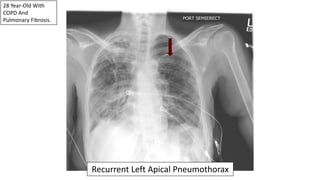

28 Year-Old With

COPD And

Pulmonary Fibrosis.

Recurrent Left Apical Pneumothorax